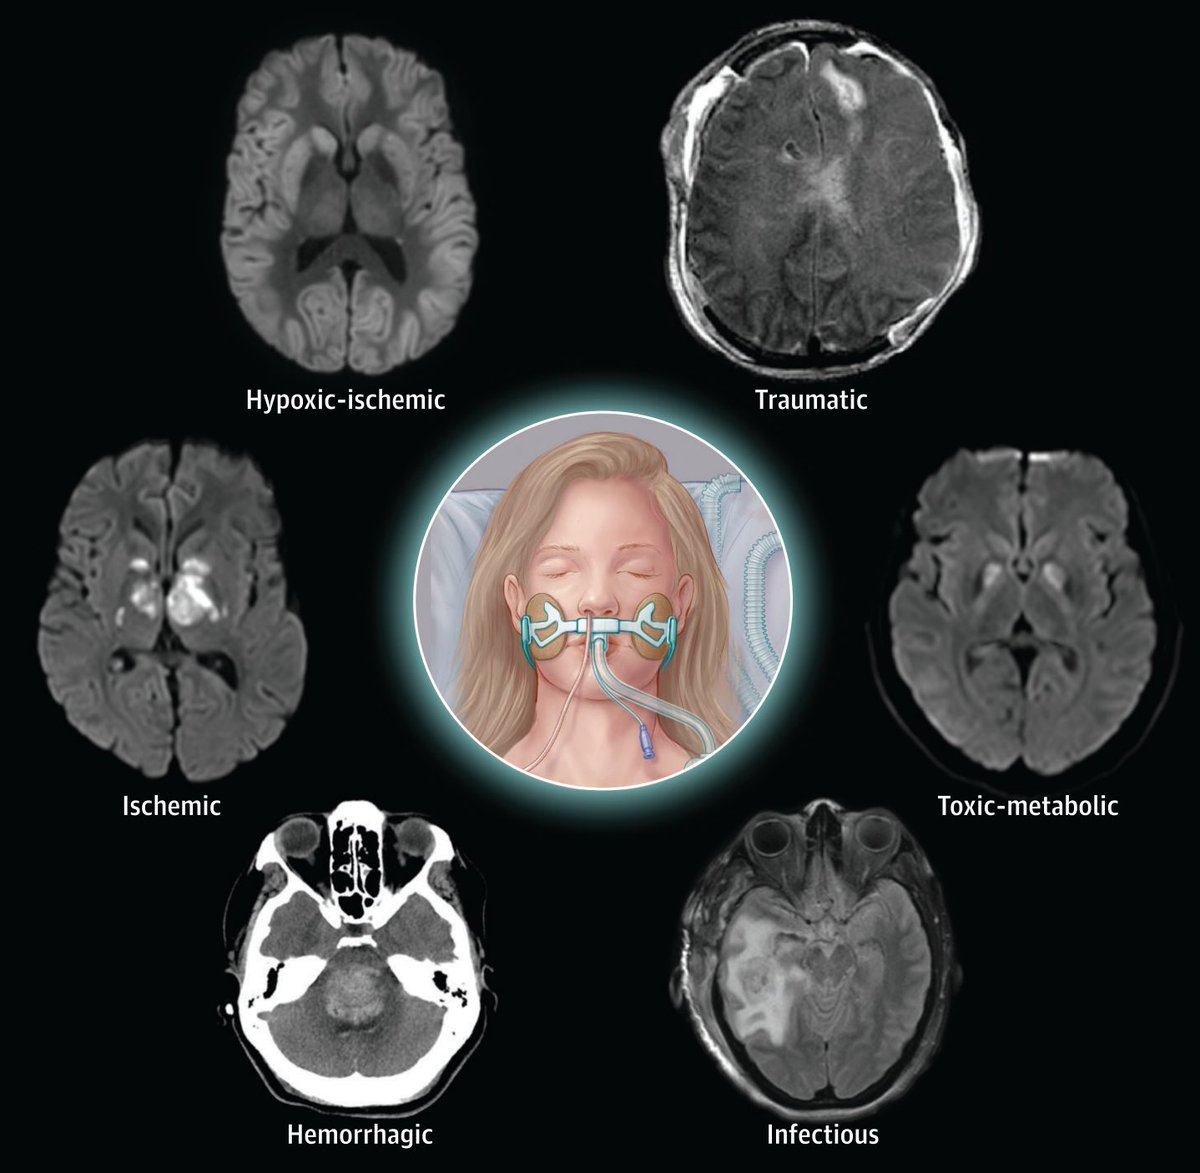

Coma has long been studied relative to specific etiologies of brain injury (e.g., anoxia, TBI, stroke). However, we can also consider coma as a final common pathway across etiologies, and there are fundamental principles of neuroprognostication that generalize across them. /2 Image